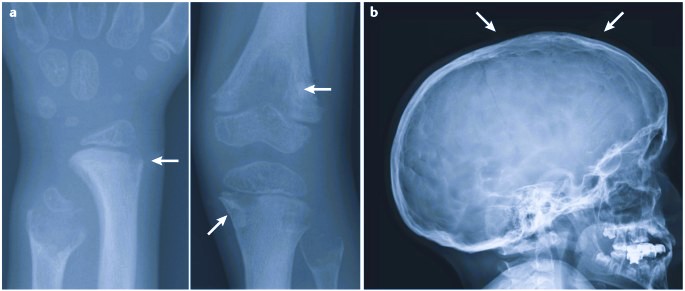

Delayed or impaired bone development

Weak and fragile bones

Pain and fractures